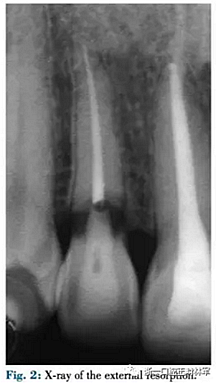

42歲需要牙頸部修復(fù)的女性患者(圖1)。16歲時(shí)上頜側(cè)切牙外傷史,根管治療時(shí)有牙外吸收(圖2)。由于其存在充足的牙體組織因此決定使用修復(fù)手段而非種植。修復(fù)方式取決于暴露的吸收邊緣,傳統(tǒng)多使用冠延長(zhǎng)術(shù),但在微笑美學(xué)區(qū)較困難。因此在第一階段進(jìn)行正畸緩慢牽引來(lái)排齊并增加軟組織量,后期結(jié)合纖維環(huán)切術(shù)進(jìn)行快速牽引牙根,使用舌側(cè)矯治器。

該患者使用舌側(cè)全口間接粘接,部分牽引12,使用0.016TMA銅鎳鈦絲(圖3,4,5)。開(kāi)始階段實(shí)現(xiàn)緩慢牽引使12頰側(cè)齦緣更接近切端,隨后采用纖維環(huán)切術(shù)進(jìn)行快速牽引以暴露損害邊緣(圖6)。